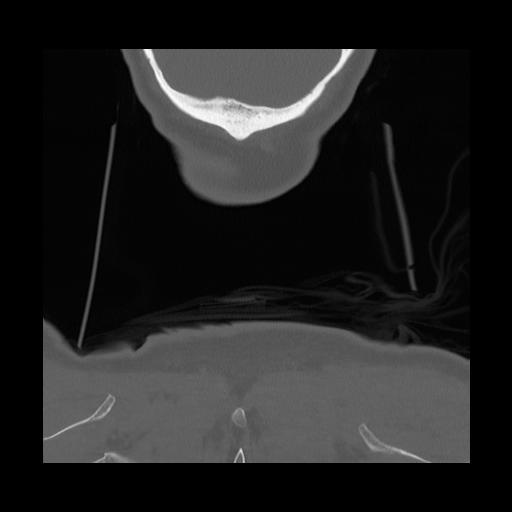

16 HUESO,,Coronal,2.000,HUESO,Coronal,